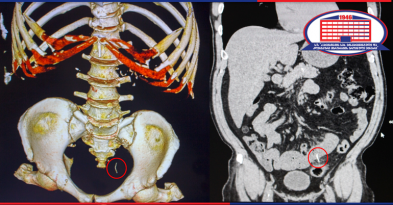

პაციენტს ჭია ნაწლავი (აპენდიქსი) უჩვეულო ადგილას ჰქონდა – რთული კლინიკური შემთხვევა, რომლის მართვაც მხოლოდ ქირურგიის ეროვნულ ცენტრში შეძლეს!

ქირურგიის ეროვნულ ცენტრში უჩვეულო კლინიკური შემთხვევა დაფიქსირდა.